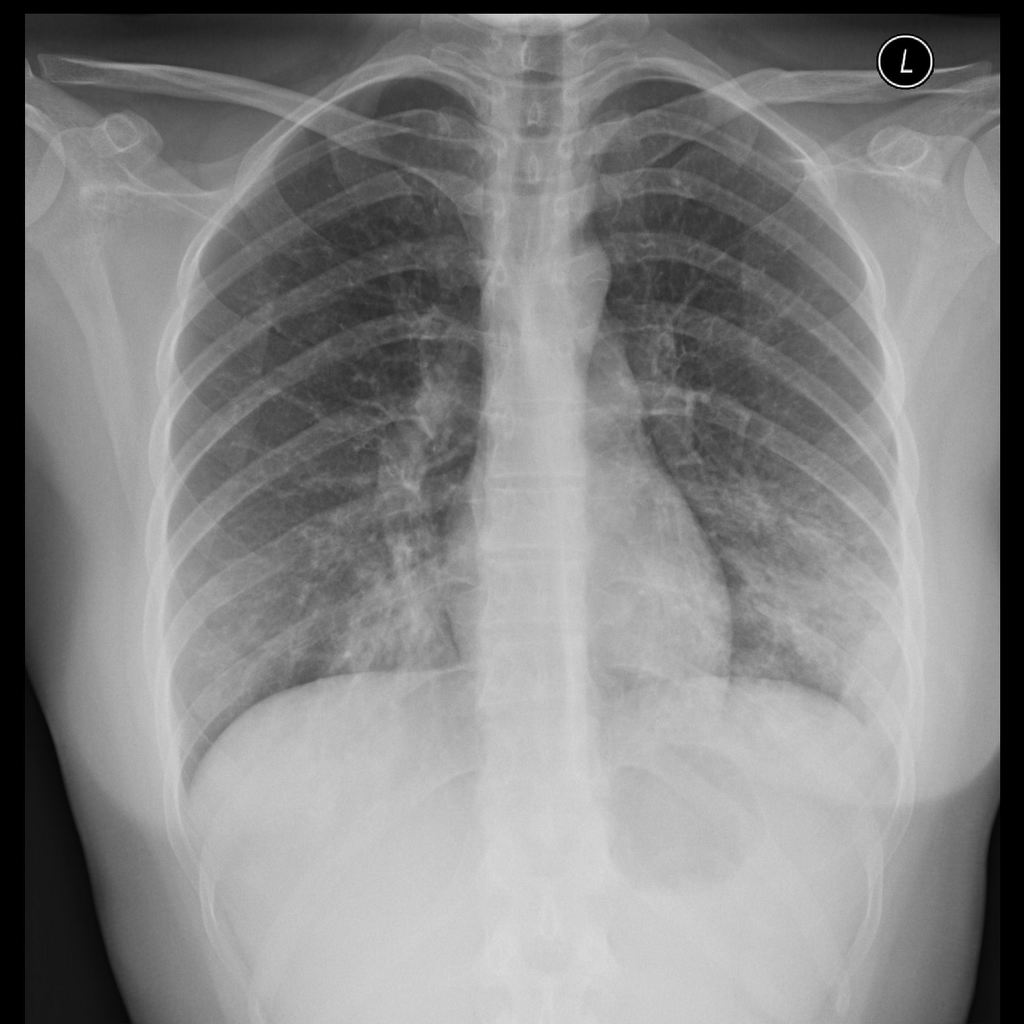

- Neumonía intersticial focal o difusa

- El término neumonía atípica (neumonía intersticial) fue inicialmente aplicado al aspecto clínico y radiográfico de la infección pulmonar que no se comporta ni se parece a la causada por S. pneumoniae. En la literatura, el término "neumonía atípica" (en oposición a "neumonía bacteriana") todavía se usa ampliamente, aunque técnicamente es incorrecto. Muchos organismos causantes se identifican como bacterias, aunque tipos inusuales (Mycoplasma es un tipo de bacteria sin pared celular y Chlamydia son parásitos intracelulares). Por lo tanto, es importante darse cuenta de que el término 'neumonía atípica', si se basa más correctamente en el tipo subyacente de patógeno causante, no solo se refiere a un patrón intersticial (neumonía por Pneumocystis jiroveci, ciertas infecciones virales sino también infecciones que se presentan con consolidación densa como como Legionella, Mycoplasma, Chlamydia, etc.). Las causas habituales de neumonía intersticial son las infecciones virales y por micoplasmas que se presentan radiográficamente con pequeñas opacidades heterogéneas focales o difusas.